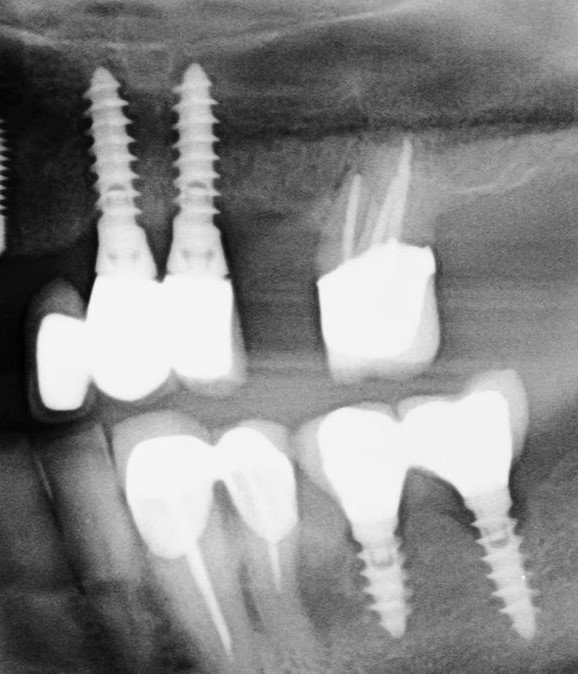

Buenas tardes, Necesitamos averiguar la marca del Implante en 46. Según nos dice el Paciente se lo puso en 2017. Muchas gracias. Un saludo.

Son implantes de conexión externa, y necesito saber qué tipo de pilares corresponde a estos implantes, gracias